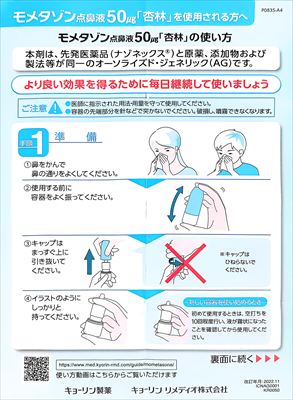

22.10.29 鼻炎薬吸引 モメタゾン点鼻液50μg 噴霧用 5mg10g 杏林 56噴霧用